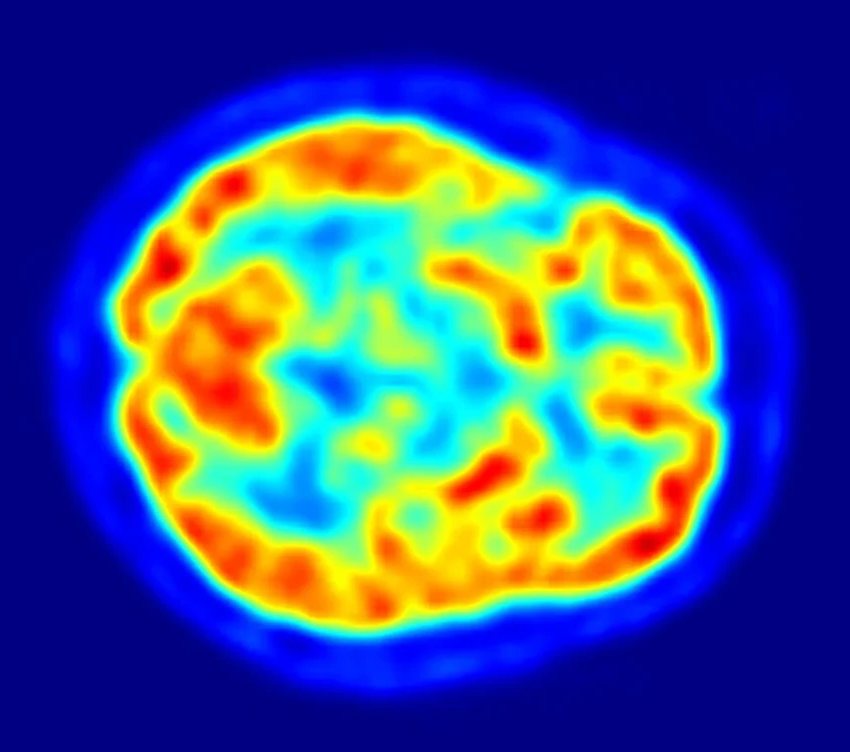

Анализ МРТ-снимков огромной армии добровольцев выявил пять чётких паттернов, по которым мозг уменьшается с годами или под натиском нейродегенеративных болезней. Эти паттерны не просто абстракция — они напрямую связаны с факторами риска, которые частично в нашей власти. Работа, занявшая у команды около восьми лет, опубликована в авторитетном Nature Medicine.

Три из пяти выявленных паттернов оказались тесно связаны с деменцией и её предвестником — лёгкими когнитивными нарушениями. Но что ещё важнее — эти модели оказались предсказательными. «Если вы хотите спрогнозировать переход от нормы к лёгким нарушениям, одна из моделей даёт самый точный ответ», — объясняет Давацикос. Другие паттерны были ассоциированы с болезнями Паркинсона и Альцгеймера. А комбинация трёх определённых моделей и вовсе указывала на резко повышенный риск смерти. Сильно, правда?

Учёные также обнаружили чёткие связи между каждым «узором старения» и конкретными факторами: злоупотреблением алкоголем, курением, определёнными генетическими маркерами и биохимическими показателями крови. Давацикос полагает, что это отражает простую истину: общее здоровье тела неотделимо от здоровья мозга. Повреждение других органов обязательно аукнется и в черепной коробке.